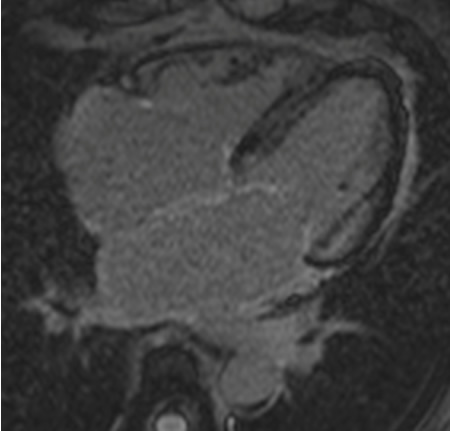

Ressonância nuclear magnética cardíaca (RNMC) de paciente com infiltração amiloide cardíaca. Após injeção de contraste de gadolínio, na fase tardia há um anel basal subendocárdico no ventrículo esquerdo (corte de 4 câmaras)

Do acervo de Dr Jessica Webb; usado com permissão